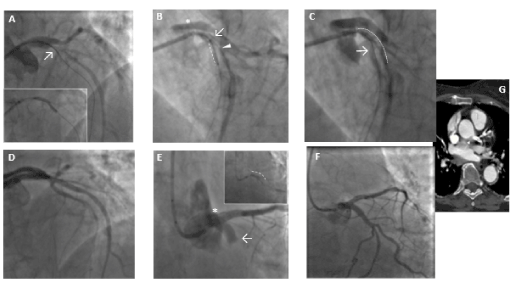

A 58-year-old non-smoker male with family history of coronary artery disease was referred because of progressive angina during moderate exercise and a positive stress test with 2 mm ST depression from lead V1 to V5. Coronary angiography performed through right radial access demonstrated a significant mid RCA stenosis (Figure 4 – Panel A) associated with severe left coronary system calcification, a critical stenosis of mid LCX (Figure 4 – Panel B), and a severe loop of the proximal LAD followed by critical stenosis of mid-distal LAD (Figure 4 – Panel C). The LM was catheterized with a 3.5 EBU 6Fr guiding catheter, and a Balance Middleweight guidewire (Abbott Diagnostics, Lake Forest, Illinois) was placed in the distal LAD. After pre-dilatation with an Euphora 2.5 x 20 mm PTCA balloon at 12 atm (Medtronic, Santa Rosa, CA, USA) we tried to implant a DES Onyx 3x23 mm which was not able to cross the lesion. Thus, a 3x12 mm lithotripsy balloon (Shockwave Medical Inc) was placed across the lesion with application of 80 pulses at 4, 6 and 8 atm (Figure 4 – Panel D insert). At control angiography an antegrade and retrograde dissection of the entire LAD segment was evident (Figure 4 – Panel D) with involvement of LM (Dunning classification type II). The patient experienced acute chest pain and progressive hypotension requiring vasoactive drug support, emergency intubation and intra-aortic balloon pump (IABP) placement (Figure 4 – Panel E). Subsequently, also LCX occluded due to extension of the dissection flap to LCX ostium. This event was followed by ventricular fibrillation storm and development of severe cardiogenic shock. External heart massage followed by several DC shocks were immediately deployed to the patient. Then, an Impella 2.5 heart pump device (Abiomed Inc., Danvers, MA, USA) was placed in the left ventricle for percutaneous mechanical circulatory support (Figure 4 – Panel F). However, cardiogenic shock persisted, and several ventricular fibrillation episodes continued to occur. Thus, a veno-arterial extracorporeal membrane oxygenation (VA-ECMO) was placed with immediate improvement of patient’s hemodynamic and stabilization of the ventricular electric storm. A transthoracic echocardiography was then performed to establish the integrity of the aortic valve. The time interval for complete hemodynamic stabilization was almost 2.5 hours. At this point, the EBU catheter, lost during the reanimation manouvers, was re-advanced into the LM ostium and advancement of a Fielder XT-A wire (Asahi Intecc Co., Ltd. Aichi, Japan) through the true-false lumen was obtained with re-establishment of a TIMI-1 distal flow on LAD. The LM ostium and the entire LAD was then dilated with an Euphora balloon 3.5x20 mm at 12 atm as in a “knuckle technique” fashion, restoring a distal TIMI 2 coronary flow (Figure 4 – Panel G-H). The LCX was re-opened with IVUS-guided mini subintimal and re-entry (“mini-STAR”) technique and final implantation of a Resolute Onyx DES 3x12 mm (Medtronic, Minneapolis USA) at the origin of LCX. Procedure was then completed with positioning of a Resolute Onyx DES 3.0x28 mm in the proximal part of the LAD. It was impossible to advance a second DES in the mid part of the LAD despite utilization of 6 Fr GuideLiner® catheter (Vascular Solutions Inc., Minneapolis, Minnesota, United States) due to the marked tortuosity of the vessel. At the end of the procedure LM presented a small no-flow limiting dissection which was left untreated since judged safe.  TIMI 2-3 flow in the distal bed of the LAD was present. The patient recovered for 2 weeks in the ICU and the VA-ECMO removed after one-week. Ejection fraction was 51% at 45th days and the patient were discharged at 62nd days. A coronary angiography performed 5 months for recurrence of chest pain with ECG ischemic modifications in anterior leads, demonstrated complete sealing of the LM with good patency of the LAD and LCX stents and residual significant stenosis of mid LAD, mid LCX and an FFR of 0.69 on mid RCA. In addition, a double-rail no-limiting-flow dissection in the mid and distal segment of the LAD was still present (Figure 5). The heart team decided to increase medical therapy and to wait to allow better sealing of the LAD. However, the patient, after 8 months, was submitted to double coronary bypass (LIMA-IVA, RIVA-RCA) for recurrence of several episodes of angina. He is asymptomatic since. The EF is 51% by echo examination.

Figure 4. Case-2: coronary angiography demonstrating RCA with significative mid stenosis (Panel A), LM calcification with severe stenosis of the mid LCX (Panel B) and long, significant calcific stenosis of LAD (Panel C). Lithotripsy balloon across the lesion (insert of D), antegrade and retrograde dissection of the entire LAD segment with involvement of LM (Dunning classification type II) (Panel D). IABP insertion (Panel E). Impella 2.5 heart pump device followed by ECMO (box insertion) for mechanical circulatory support (Panel F). Re-wiring of true lumen of LAD after cannulation with EBU catheter and balloon dilation of the entire vessel, restoring a TIMI 2 coronary flow (Panel G-H).

Figure 5. Case-2: five mos follow-up coronary angiography showed complete sealing of the LM with good patency of the LAD and LCX stents with a double-rail dissection not-limiting-flow in the mid and distal segment of the LAD suggesting not complete healing of the dissection plane.